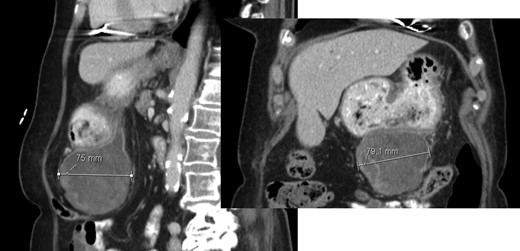

A 78-year-old woman with past medical history of hypertensive cardiopathy and bearer of a pacemaker, was referred to our Hepatobiliary Unit with diagnose of a liver mass discovered on CT scan, which was performed after complaints of nausea and postprandial infarction. CT scan (Fig. 3) showed a voluminous heterogeneous, lobed mass, displaying heterogeneous uptake contrast, relatively vascularized, localized in segment 1, with exophytic growth to the left lobe, with 18.5 × 13.8 × 15.6 cm; the tumor caused deviation of the stomach to the left.

AP-CT – voluminous heterogeneous mass in segment 1 with 18.5 cm in diameter.